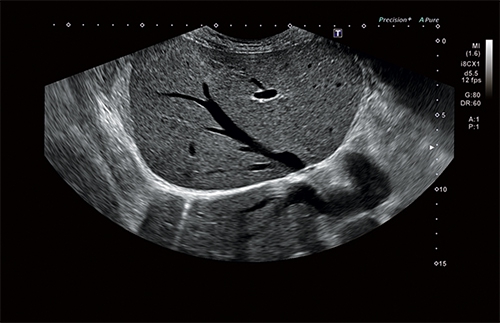

• Режим Luminance для получения качественного изображения плода в первом триместре с помощью трехмерной реконструкции

4D

Объемное сканирование в реальном времени больше не фантастика, а впечатляющее достижение современных технологий. С помощью сканирования этого типа вы сможете рассмотреть даже самые мелкие детали изображения под любым требуемым для проведения исследования углом.

Объемная визуализация сердца плода

Эта впечатляющая функция исследования сердца плода основана на достижениях технологии 4D и связана с пространственно-временной корреляцией получаемого вами изображения. Теперь вы сможете сохранять полученные данные для их последующего изучения в динамике, а также просмотра в двухмерных и трехмерных режимах.